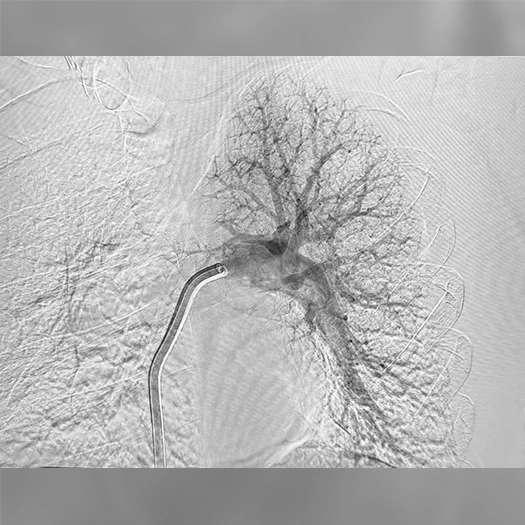

Initial access was obtained via the right common femoral vein using an 8-F sheath that was upsized to a 17-F Element™ sheath, and Lightning Flash 3.0 was advanced over a 0.035-inch wire into the right pulmonary artery (PA). With the Lightning Flash 3.0 aspiration catheter positioned, the 0.035-inch wire was removed and 10 mL of contrast was loaded into the catheter, followed by a 20-mL saline flush to deliver the contrast into the right PA vasculature. Angiography demonstrated an occlusion in the right upper lobar artery.

The aspiration catheter was then torqued and positioned proximal to the occlusion, at which point aspiration was initiated. The Lightning Flash console illuminated yellow, and the valve cadence increased, indicating catheter engagement with thrombus. The Lightning Flash 3.0 catheter was retracted toward the right main PA. Upon retraction, a large thrombus burden was seen being evacuated through the system. Subsequently, the Lightning Flash system transitioned to sampling mode, indicating the target segment had been cleared. Repeat contrast injection via the Lightning Flash catheter confirmed resolution of thrombus.

Pre: Right pulmonary angiogram demonstrates an occlusion in the right upper lobar artery.